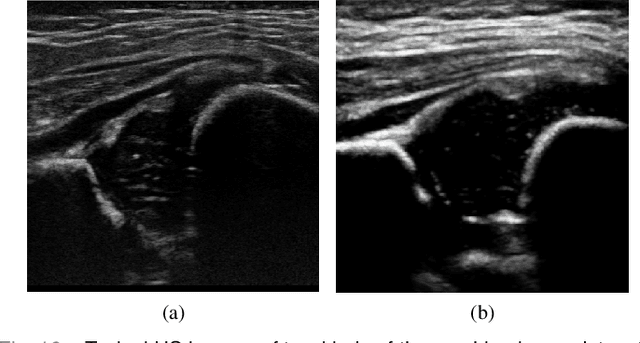

Abstract:The ultrasound (US) screening of the infant hip is vital for the early diagnosis of developmental dysplasia of the hip (DDH). The US diagnosis of DDH refers to measuring alpha and beta angles that quantify hip joint development. These two angles are calculated from key anatomical landmarks and structures of the hip. However, this measurement process is not trivial for sonographers and usually requires a thorough understanding of complex anatomical structures. In this study, we propose a multi-task framework to learn the relationships among landmarks and structures jointly and automatically evaluate DDH. Our multi-task networks are equipped with three novel modules. Firstly, we adopt Mask R-CNN as the basic framework to detect and segment key anatomical structures and add one landmark detection branch to form a new multi-task framework. Secondly, we propose a novel shape similarity loss to refine the incomplete anatomical structure prediction robustly and accurately. Thirdly, we further incorporate the landmark-structure consistent prior to ensure the consistency of the bony rim estimated from the segmented structure and the detected landmark. In our experiments, 1,231 US images of the infant hip from 632 patients are collected, of which 247 images from 126 patients are tested. The average errors in alpha and beta angles are 2.221 degrees and 2.899 degrees. About 93% and 85% estimates of alpha and beta angles have errors less than 5 degrees, respectively. Experimental results demonstrate that the proposed method can accurately and robustly realize the automatic evaluation of DDH, showing great potential for clinical application.